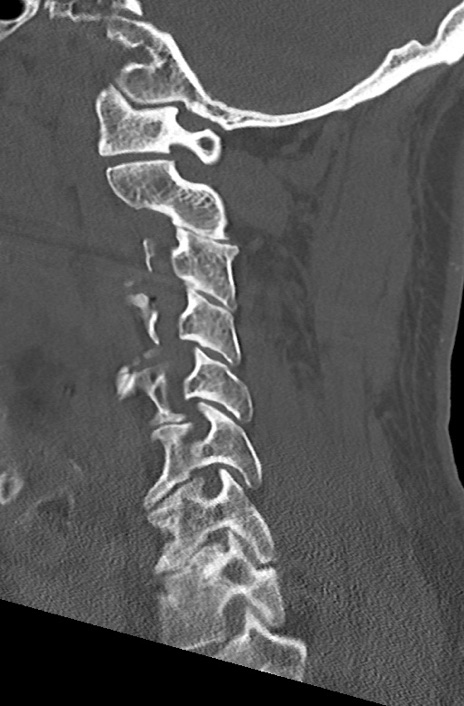

頚椎CT

矢状断像と横断像